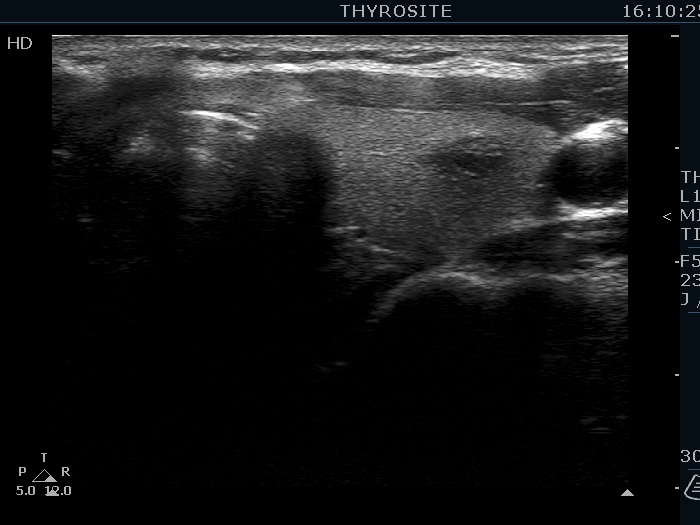

Ultrasonography. The thyroid was echonormal. There were several hypoechoic nodules in the left lobe. The middle one had back wall cystic figures. There were 3 or four discrete, deeply hypoechoic lesions above and lateral to the left lobe in the neck. One of them presented with a hilum-like figure while the others lacked hilum.

The lymph nodes had a non-typical presentation. They lacked a regular hilum.